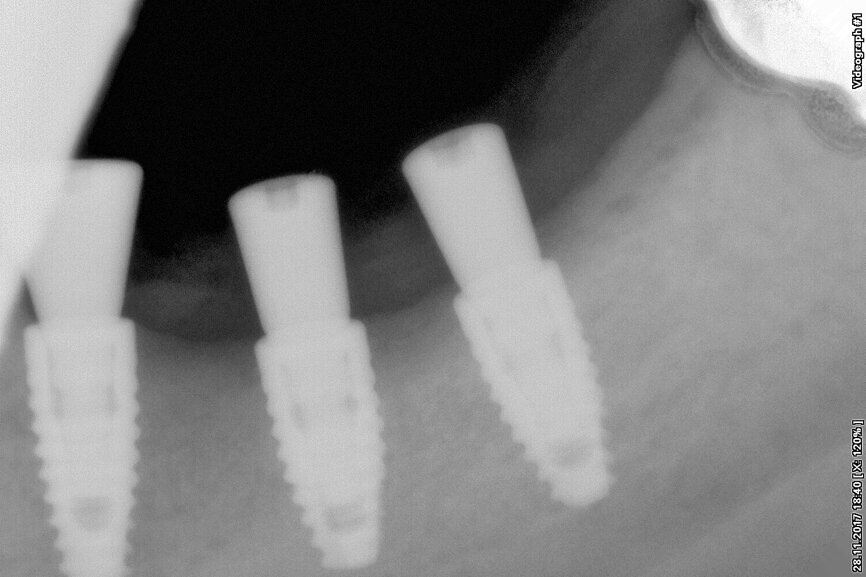

Fig. 5: New bone around implants.

Digital radiographic images were taken at the time of surgery, 24 hours postoperatively and one month later in order to evaluate implant success (Figs. 6, 7, 11, 13, 15 & 20). In none of the patients inflammatory processes were found and all implants remained stable.